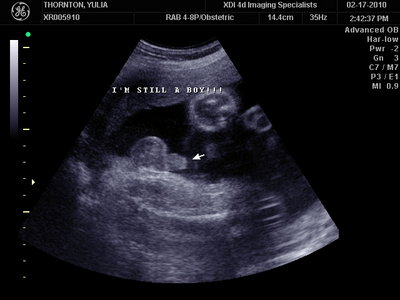

А это в 30 недель

| Вложения: |

MY BABY SONO!_20.JPG [ 94.63 КБ | Просмотров: 1362 ]

Sweetheart75 писал(а): Ну ладно, тогда и я нашего писюна покажу  Надеюсь, Джеффри на меня не обидится Вот это в 23 недели: (там оборудование переключалось из режима 3Д в обычный 2Д) Oоо, такое достоинство невозможно не заметить  А в 30 недель так вообще!